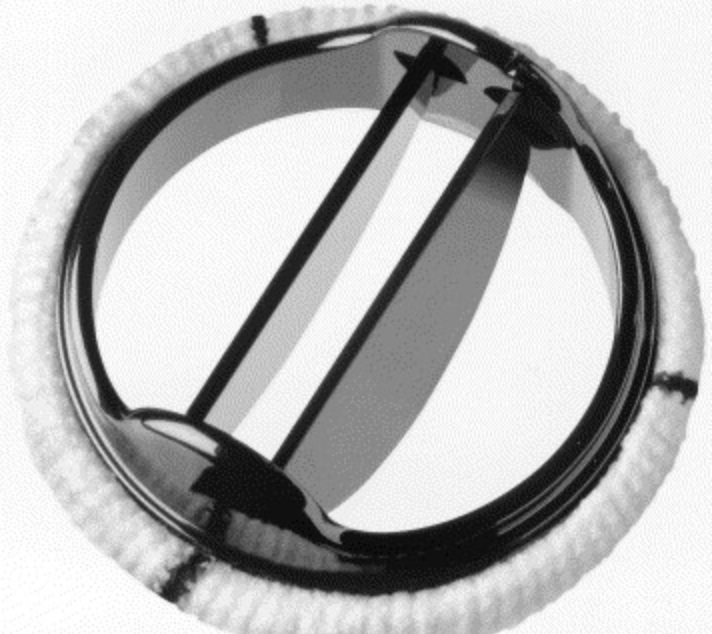

Hastalıklı kapağın değiştirilmesinde kullanılan takma (protez) kapaklar arasında en sık kullanılan mekanik kapaklar ve hayvanlardan alınan doku kapaklarıdır (biyoprotez kapaklar). Kapak tamiri en sık mitral kapak yetersizliğinde kapağın fazla hasar görmemiş olduğu durumlarda tercih edilebilmektedir.